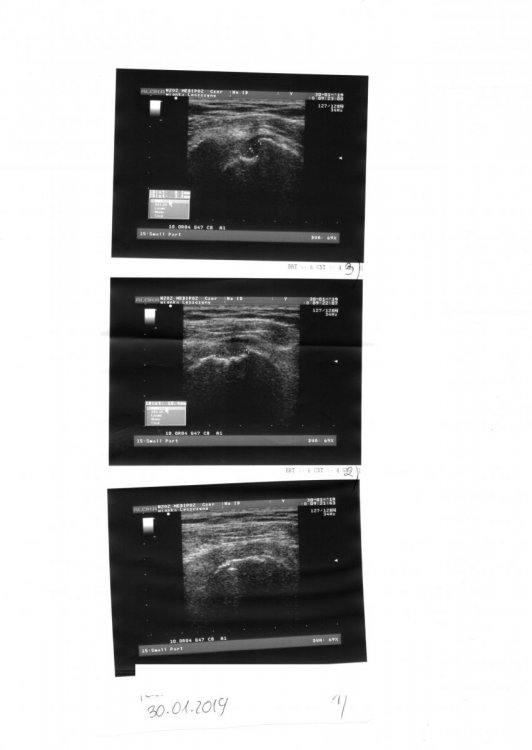

1. Witam, rok temu u mnie wykryto raka trzonu macicy G1 jestem po usunięciu, wyniki rakowe 3 miesiące temu wszystkie ok, lecz miałam uraz poprzez wywrócenie się na bark, ból przeszedł natomiast po miesiącu znowu powrócił prześwietlenie RTG nic nie wykazało wyniki krwi OK, natomiast OB podwyższone na 60 miałam wczoraj robione USB tej ręki oto wyniki czy może mi ktoś to zinterpretować i coś więcej powiedzieć bo wizytę u lekarza mam za dwa tygodnie.

2. Witam, rok temu u mnie wykryto raka trzonu macicy G1 jestem po usunięciu, wyniki rakowe 3 miesiące temu wszystkie ok, lecz miałam uraz poprzez wywrócenie się na bark, ból przeszedł natomiast po miesiącu znowu powrócił prześwietlenie RTG nic nie wykazało wyniki krwi OK, natomiast OB podwyższone na 60 miałam wczoraj robione USB tej ręki oto wyniki czy może mi ktoś to zinterpretować.